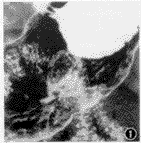

2、CT檢查:腹部CT不僅可了解腫瘤在壁內的生長情況,而且可測其CT值,了解腫瘤的組織結構,達到明確診斷的目的,有一定診斷價值,可區別脂肪與其他組織。